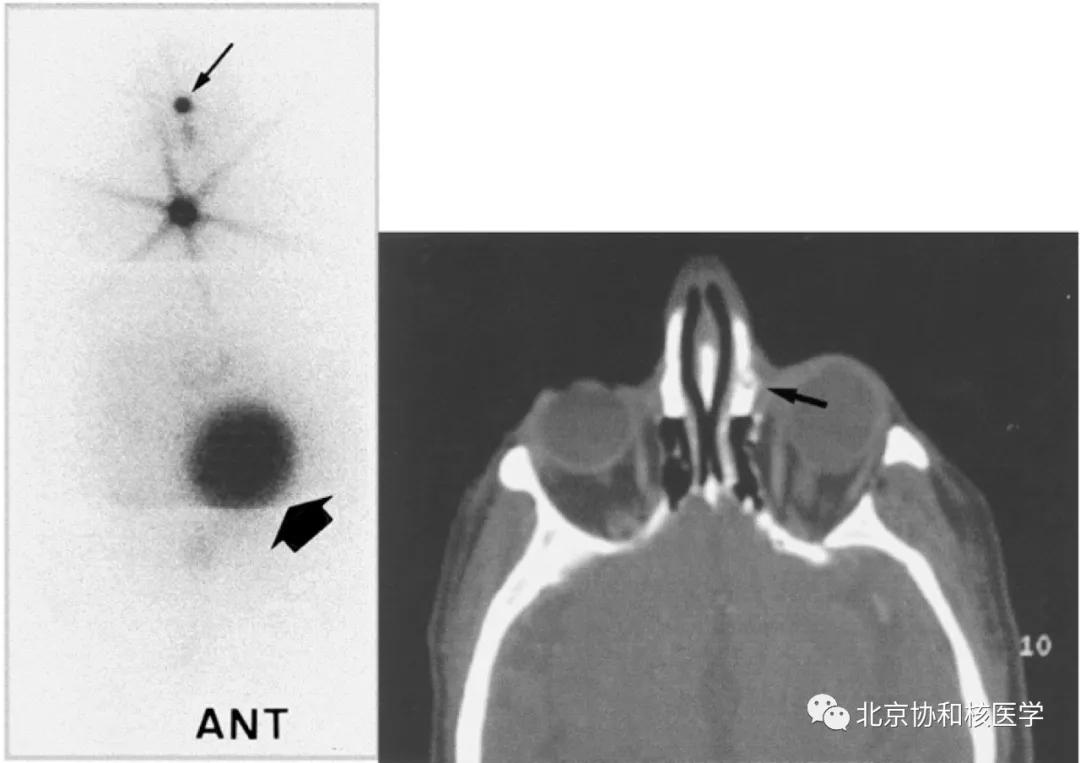

脑膜瘤所致碘摄取:

鼻骨骨样骨瘤所致碘摄取,腹部另可见由于巨大肾囊肿所致碘异常摄取: